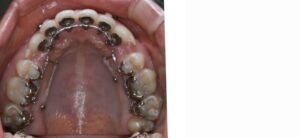

下顎左右の奥歯が失われた状態でしたが矯正治療でスペースを閉じて、上の歯は左右の小臼歯を抜歯して矯正用のアンカースクリューを併用して上の前歯を後ろに下げる治療を行いました。

結果、前歯の出っ張りが改善し自然に口を閉じられるようになり奥歯でしっかり噛める様になりました。(装置はハーフリンガル)

矯正治療中(上顎)